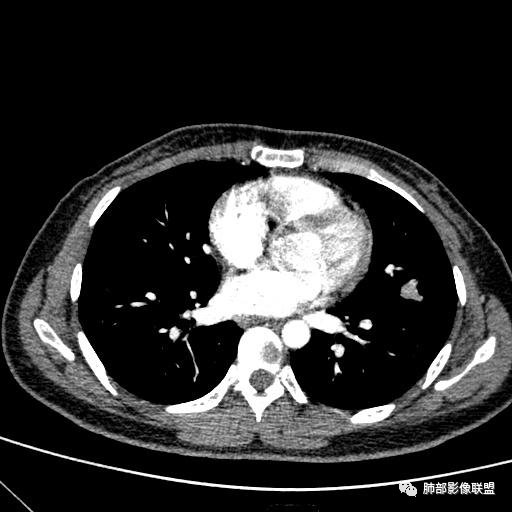

1、临床特点:30岁女性,体检发现肺部结节。

2、影像特点:左肺上叶舌段实性密度结节,边界清楚,略呈不规则三角形,边缘多平直,未见分叶、毛刺及明显收缩。密度均匀,未见钙化、脂肪密度或低密度液化空洞,持续渐进强化。未显示相关支气管及血管出入、血管贴边等。未见明确卫星病灶。双肺门及纵隔未见增大淋巴结。

3、病例小结:年轻女性,体检发现,左肺上叶舌段实性结节,边缘清楚光滑,未见分叶毛刺及收缩,亦未见边界清晰的磨玻璃晕,与支气管血管了无瓜葛等,较为符合的是肺良性结节。

3)边界清楚,未显示相关支气管及血管出入,强化明显,应当想到硬化性肺细胞瘤。

CT:形态:圆形或椭圆形结节,边界清楚,无分叶及毛刺、无胸膜凹陷征及血管集中等恶性征象,无卫星病灶,周围无纹理增多及粘连等;大小:平均直径3cm,从<1cm到>10cm均有报道;密度:均匀、软组织密度,偶有出血、囊变、钙化;强化方式:多为均匀明显强化,少数不均匀强化;其它特殊征象:血管贴边征 、空气半月征 、晕征,偶见纵隔淋巴结肿大。